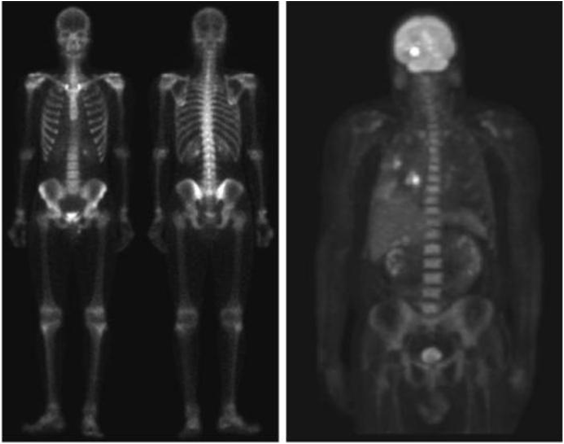

Gamma ray image

• 감마선의 투과성을 이용

• 주요 응용분야: 핵의학, 천문관측

Image

a) 환자에게 감마선을 방사하는 방사선 동위원소를 주사, 감마 검출기로써 영상을 획득 - 병소의 위치 파악에 유용 b) PET(positron emission tomography) image c) 백조자리 15,000년전의 가스성운의 감마선 영상 d) 핵반응 밸브로부터 나오는 감마선(밝은 부분)

Imaging in the radio band

• 주요 응용분야: 의학(MRI: magnetic resonance image), 천문학

인체의 MRI 무릎, 척추